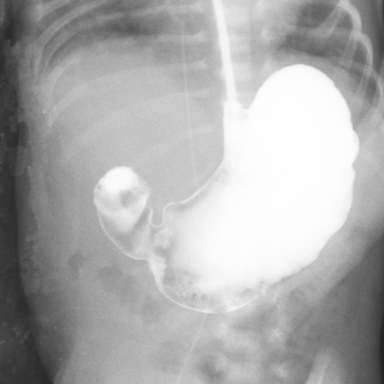

造影提示十二指肠梗阻

造影提示十二指肠梗阻 术中见梗阻部位为十二指肠降部,梗阻原因为环状胰腺